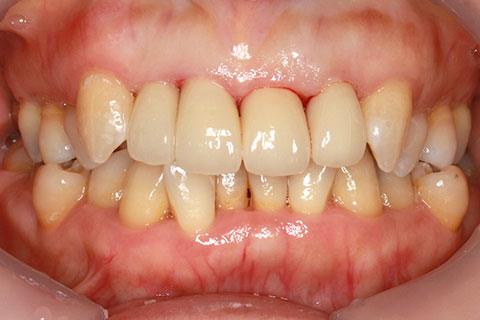

オールセラミックの症例2

- 年齢・性別

- 45歳男性

- 治療期間

- 2ヶ月

- 抜歯

- なし

- 治療費

- 70.4万円

- 備考

- 前歯8本の歯列不正によるセラミック治療

- 治療内容

- 歯質を削除し、セラミック冠をセメント合着

- 施術の副作用(リスク)

- 知覚過敏、歯髄炎、荷重負担